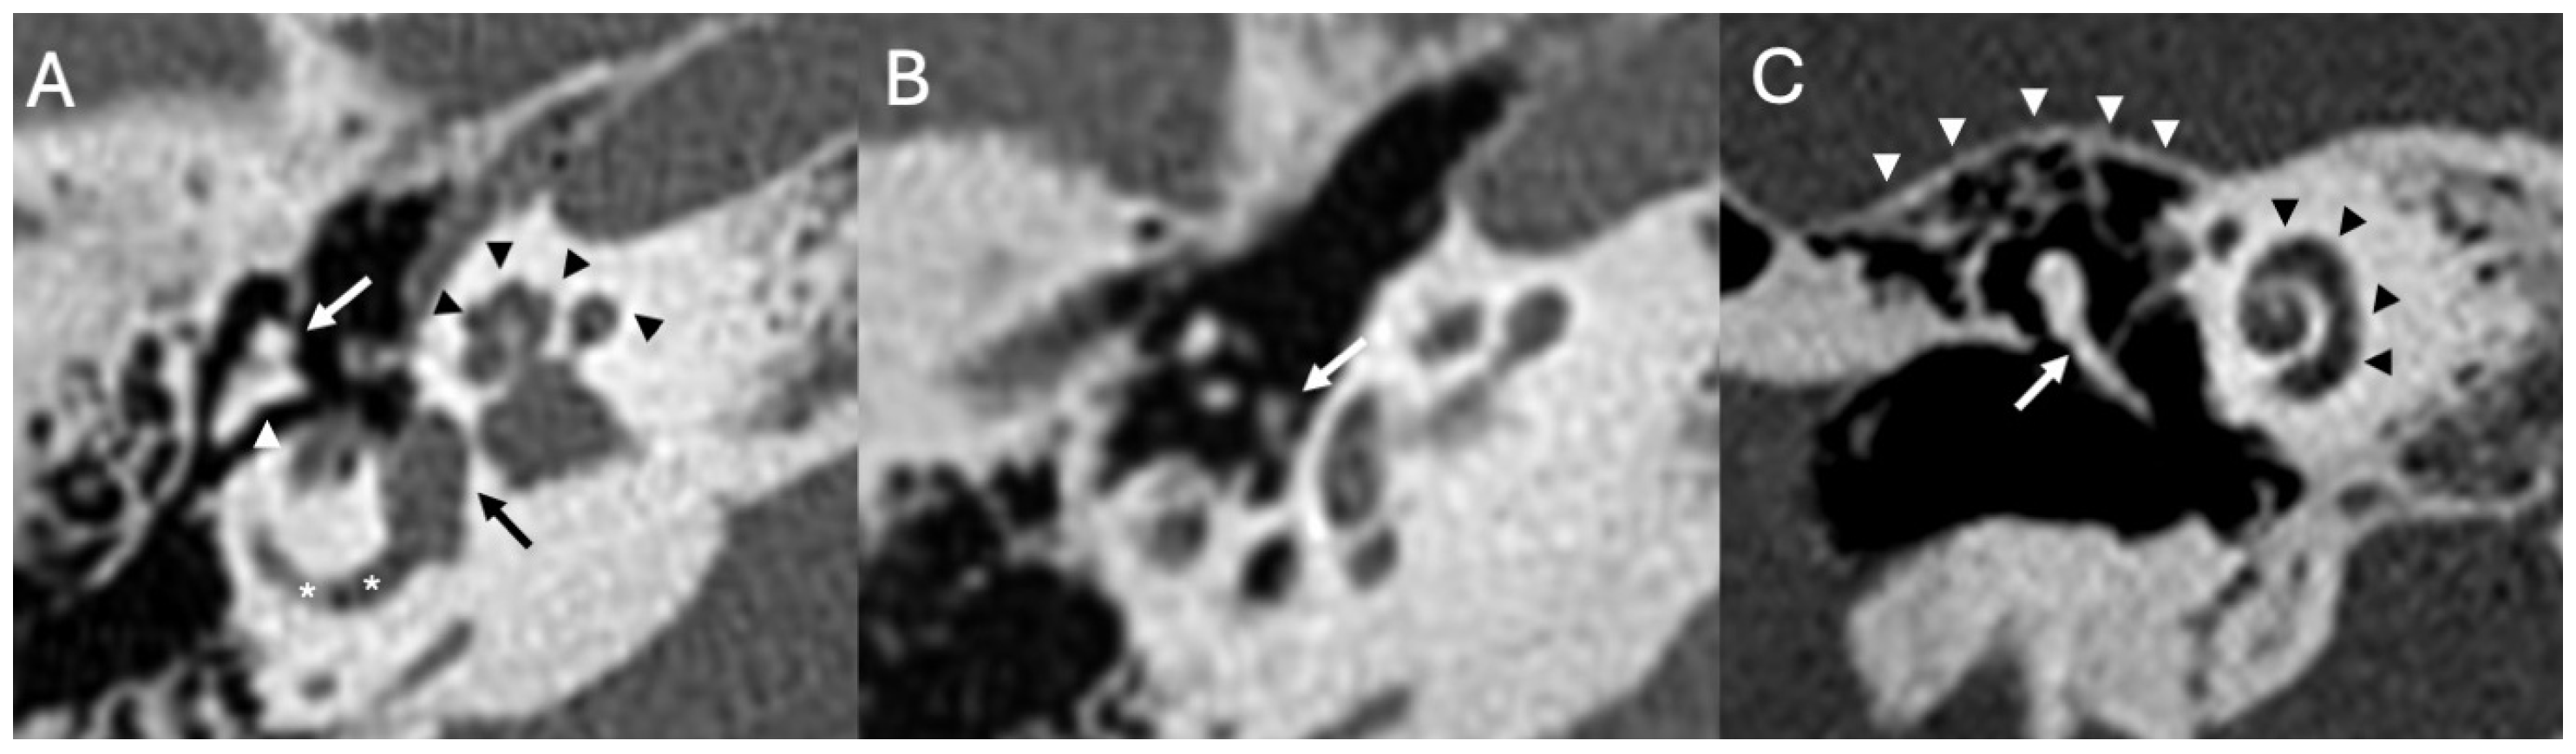

3.1. Otomastoiditis

3.1.1. Imaging

| Otomastoiditis and Otogenic Meningitis | Saat et al., 2015 [17]; Rubini et al., 2024 [18]; Vazquez et al., 2003 [19]; Bruschini et al., 2017 [20]; Barry et al., 2019 [21] | Retrospective studies, imaging reviews, and case reports | HRCT and MRI identify middle ear/mastoid infection and intracranial spread; meningitis occurs in up to 35–46% of untreated cases. |

| Bony Dehiscence/Temporal Bone Defects | Barbara et al., 2022 [22]; Sanna et al., 2009 [23]; Lim et al., 2012 [24]; Rabiei et al., 2025 [25] | Case-based studies and reviews | Tegmen tympani or semicircular canal defects create a route for meningitis and meningoencephalocele; HRCT coronal reconstructions preferred. |